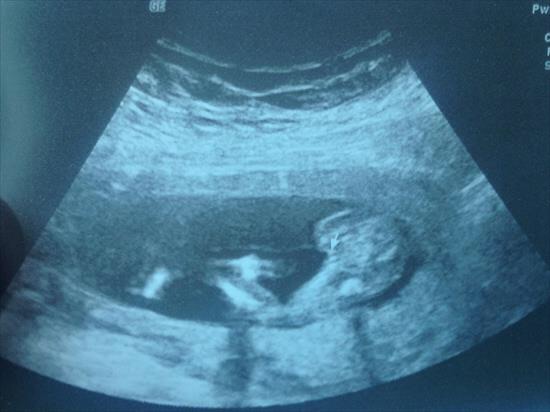

The first shot is not the typical potty shot but the arrow points at the privates and that was at 16 weeks!